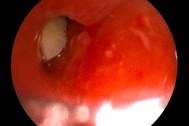

Kết quả chụp X-quang cho thấy dị vật di chuyển xuống phần ruột già của bé gái 3 tuổi.

Kết quả kiểm tra cho thấy trong phần ruột già của bệnh nhi có dị vật, nghi là chiếc vòng bạc.